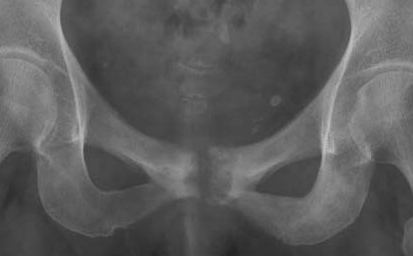

Clinical investigations, including x-ray and isotope scanning are useful in diagnosis.